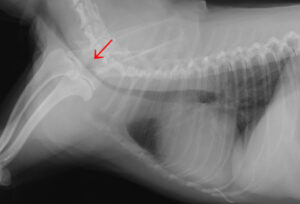

代表的なものとして「気管虚脱」があります。

特に小型犬(チワワ、ポメラニアン、ヨークシャーテリア)に多く見られます。

空気の通り道である気管がつぶれてしまい、咳などのさまざまな症状がでてきます。

ガーガーというアヒルが鳴くような特徴的な咳が見られます。

興奮時に悪化するため注意が必要です。

気管が一部つぶれてしまっている